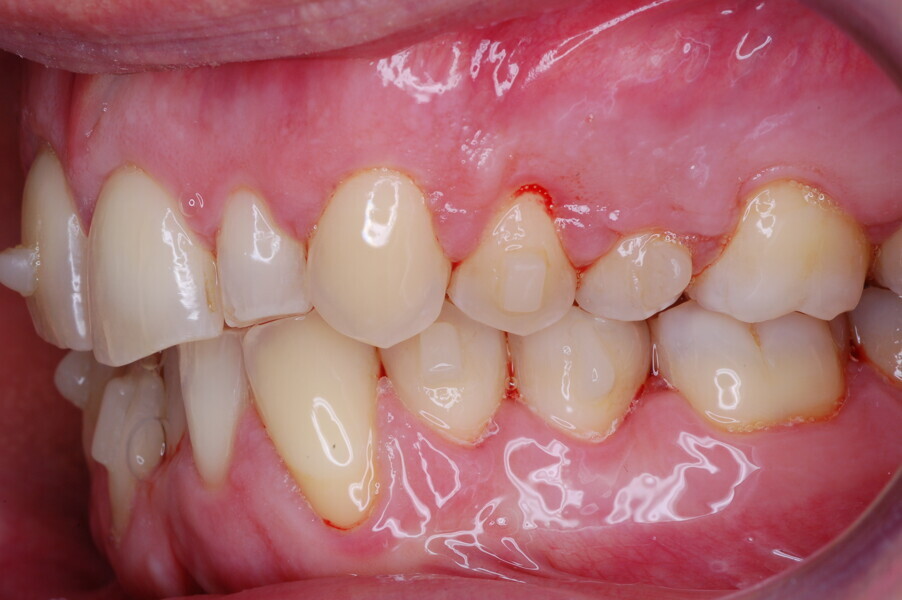

Figs. 1–8: Pretreatment facial and intra-oral photographs.

From the periodontal point of view, the patient showed a good attitude to oral hygiene, but crowding of the mandibular incisors made cleaning difficult in that area, causing plaque accumulation and localised gingival inflammation. The panoramic radiograph revealed the presence of the mandibular third molars and confirmed the absence of the mandibular right central incisor (Fig. 10).